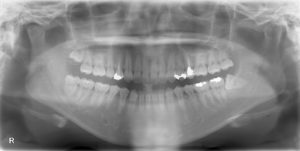

先日、左下顎の横向きに生えた親知らずと上顎の親知らずを1日で抜歯しました。(下記のレントゲンで画面向かって右の上下の一番奥の歯です。)全ての処置を30分少しで終了することができました。患者様は、不安や恐怖心もあったと思いますが、お疲れ様でした(^^)/